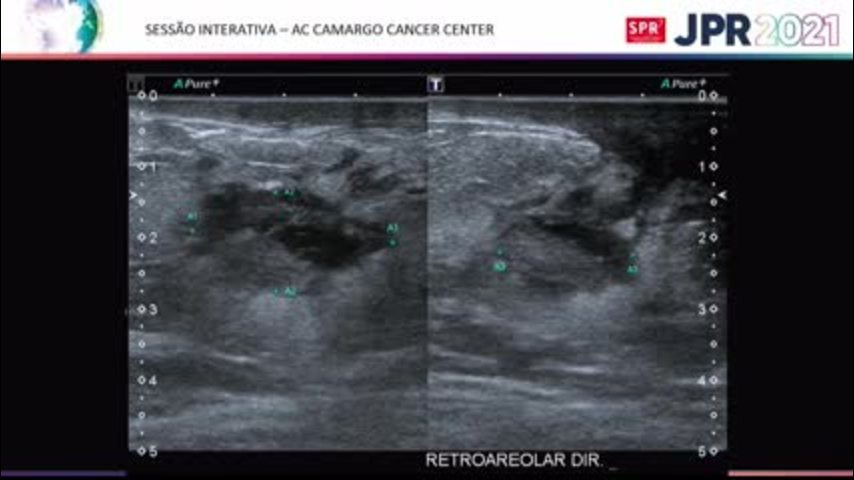

Carcinoma Inflamatório - AC Camargo